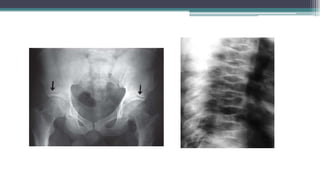

Site

• Paget’s disease can affect any bone in the skeleton but

is most frequently found in the pelvis, vertebral

column, femur, skull, and tibia.

• In most patients, it affects several sites, but, in about

20% of cases, a single bone is affected (monostotic

disease).

Workup

The diagnosis of Paget’s disease is primarily radiological

• Xray

Early disease—primarily lytic

Combined phase (mixed lytic and sclerotic

Late phase—primarily sclerotic

• An isotope bone scan is frequently helpful in assessing the extent.

• In active disease, plasma alkaline phosphatase activity is usually

(85%) elevated. An exception to this is in monostotic disease

when there may be insufficient bone involved to raise the

enzyme.